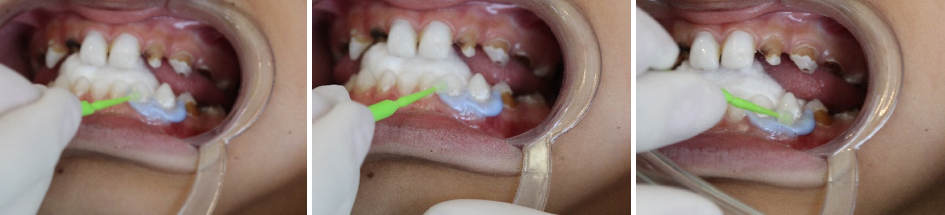

Perfurou-se a cápsula prateada com o microaplicador prateado com movimentos circulares, aplicou-se o produto sobre as lesões por 60 segundos. (foto 10, 11)

Logo após, perfurou-se a cápsula verde com o microaplicador verde com movimentos circulares e aplicado o produto em quantidade generosa, até que o produto esbranquiçado ficasse transparente. (foto 12, 13, 14)